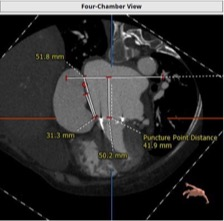

CT评估

衰败的二尖瓣瓣膜支架内径为27mm,真实内径为25mm,高度为18mm,拟选用爱德华THV 26mm SAPIEN 3瓣膜。

房间隔穿刺高度为41.9mm。

房间隔拟穿刺位置